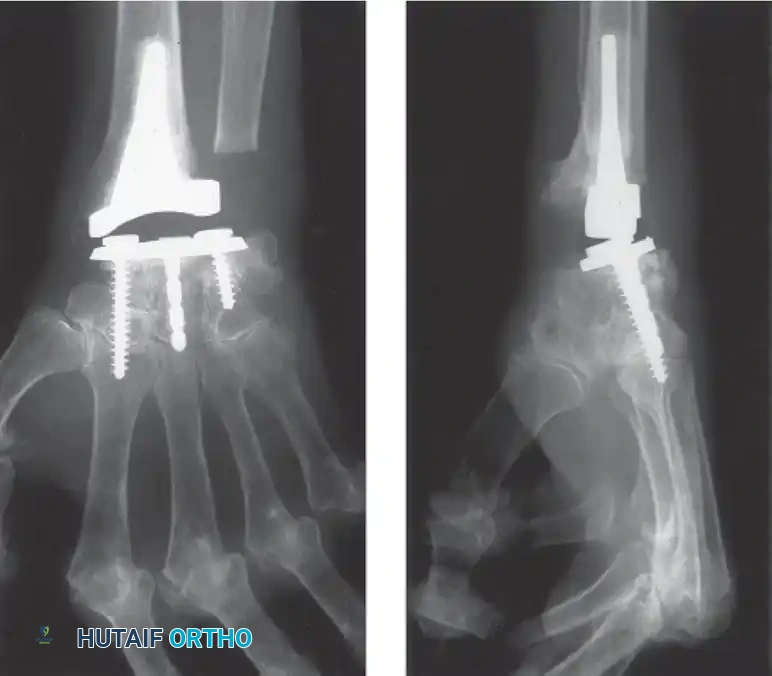

Total Wrist Arthroplasty (TWA)

Total joint arthroplasty offers the distinct advantages of preserving functional motion, providing a fixed fulcrum for tendon excursion, and achieving stable fixation. Modern designs are generally semi-constrained to allow for physiologic kinematics while preventing dislocation.

Image

Implants such as the Meuli, Volz, and Biaxial wrist prostheses have shown excellent early to mid-term results in pain relief and motion preservation. However, the Achilles heel of TWA remains distal component loosening. The carpal bones in RA are often osteopenic and cystic, providing poor purchase for the distal pegs or screws.

Complications, including distal loosening, subsidence, and periprosthetic fracture, lead to an overall revision rate of 9% to 35%. Adequate muscle balance, correctable preoperative wrist contractures, and meticulous surgical technique are absolute prerequisites for a successful TWA.